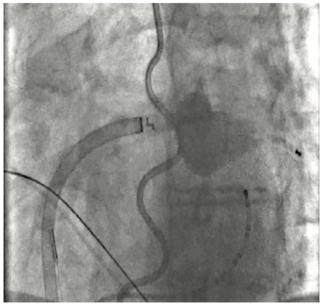

Dr Venkataraman presents his method for performing cryoballoon ablation for the treatment of symptomatic atrial fibrillation without the need for IV contrast medium.